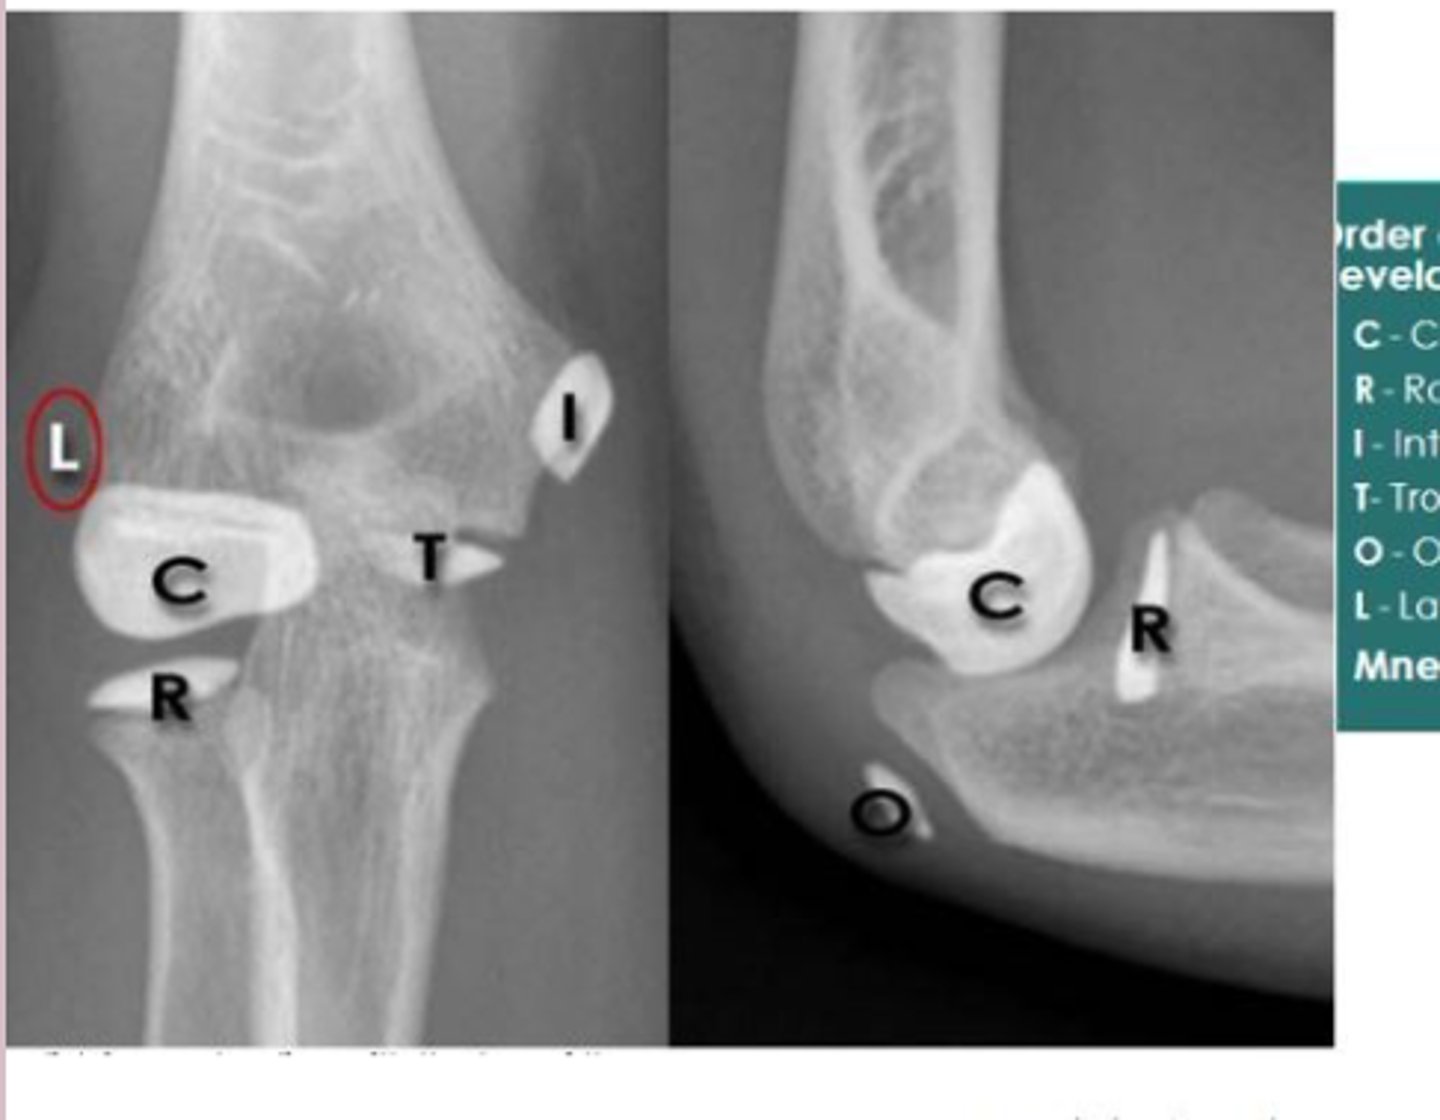

elbow

knowt flashcard image

32

New cards

elbow lateral